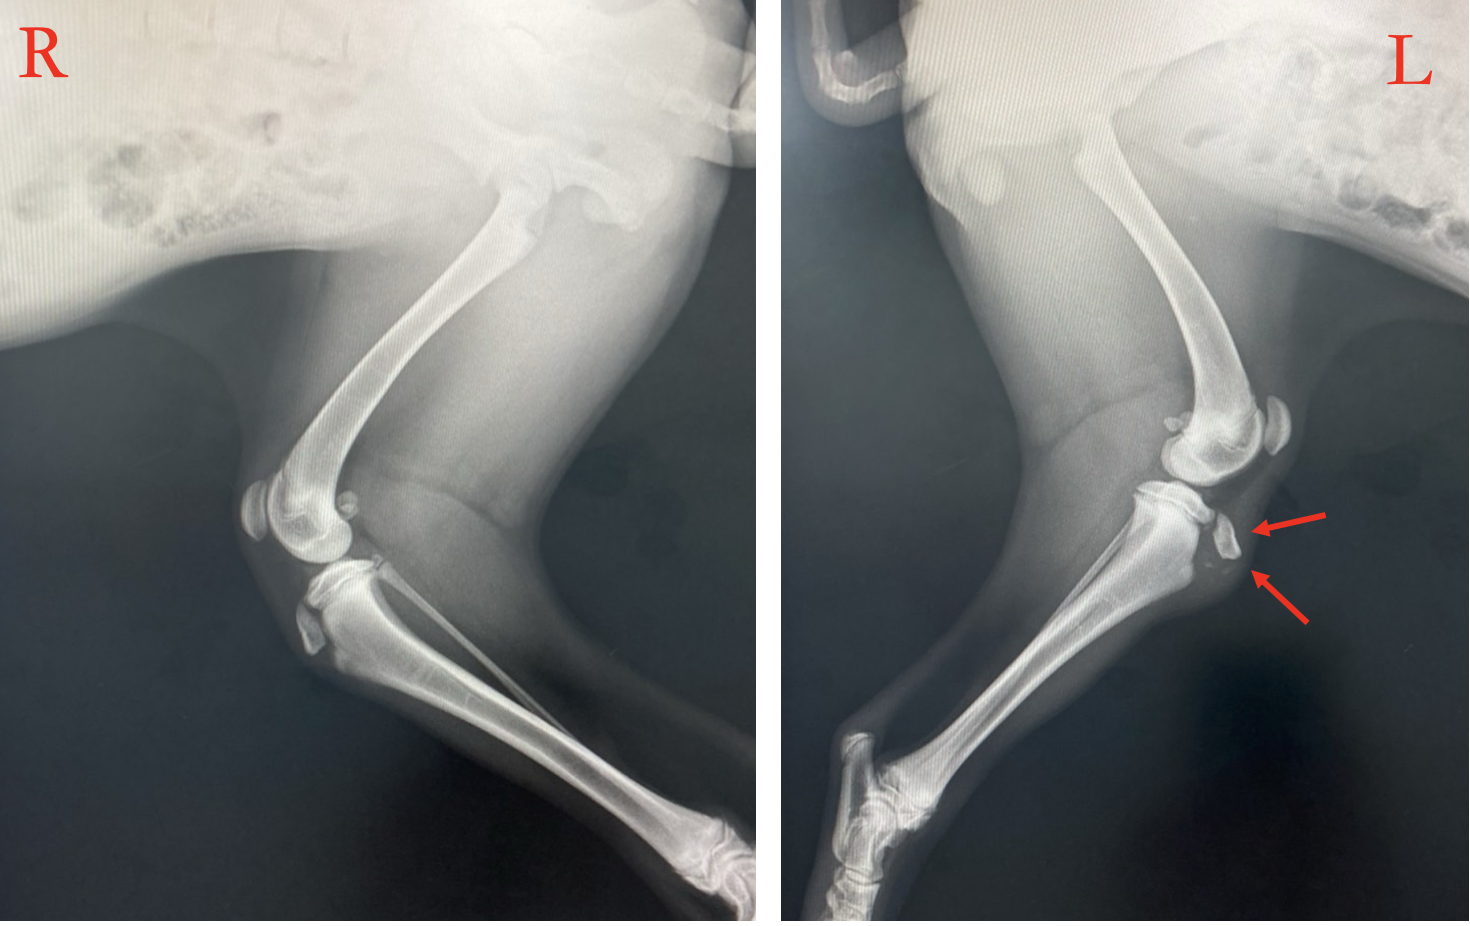

肘頭骨折

橈尺骨折(海面骨移植)